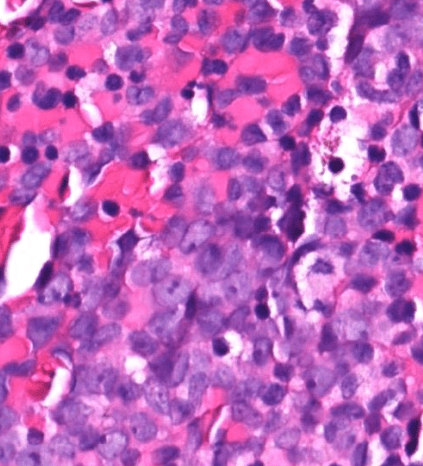

endometrial cancer